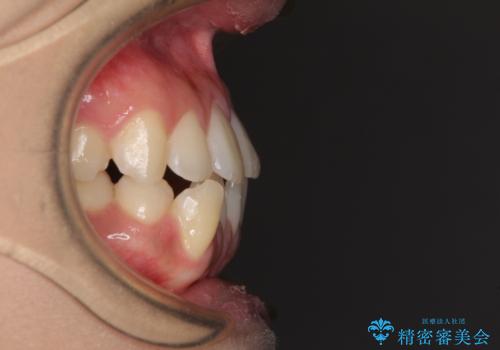

- 上下のデコボコと奥歯の咬みにくさを気にして来院された患者様です。

上顎骨の幅が下顎骨よりも小さく受け口傾向であったため、拡大装置により上顎骨の骨幅を広げて上下関係を改善し、その後インビザラインにて歯並びを整えることとしました。

下顎歯列は上顎歯列内に収まるように並んでいますが、上顎骨の幅が狭いと、下顎臼歯が全体的に舌側に傾斜した歯列となってしまいます。

舌側に傾斜した歯列は奥歯に力の負担がかかりやすく、歯磨きがしにくいなどの問題があるため、上顎骨拡大により舌側傾斜を改善することが可能となります。